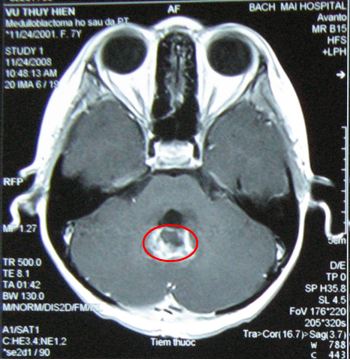

Trên hình ảnh cộng hưởng từ sau xạ trị tổn thương u đã thu nhỏ hơn kích thước u 0,5cm.

Sau điều tri: tổn thương còn lại rất nhỏ đường kính 0,5c

m

Sau điều trị, tổn thương u đã tan biến hoàn toàn